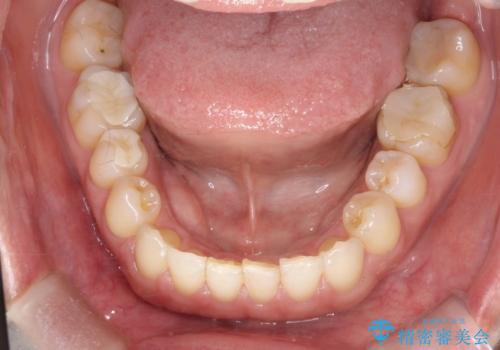

- 右上の前から2番目と3番目の歯が内側に引っ込んでしまっているのを主訴に来院されました。

右上の2番目と3番目のはが前後反対にかんでしまっている状態でした。